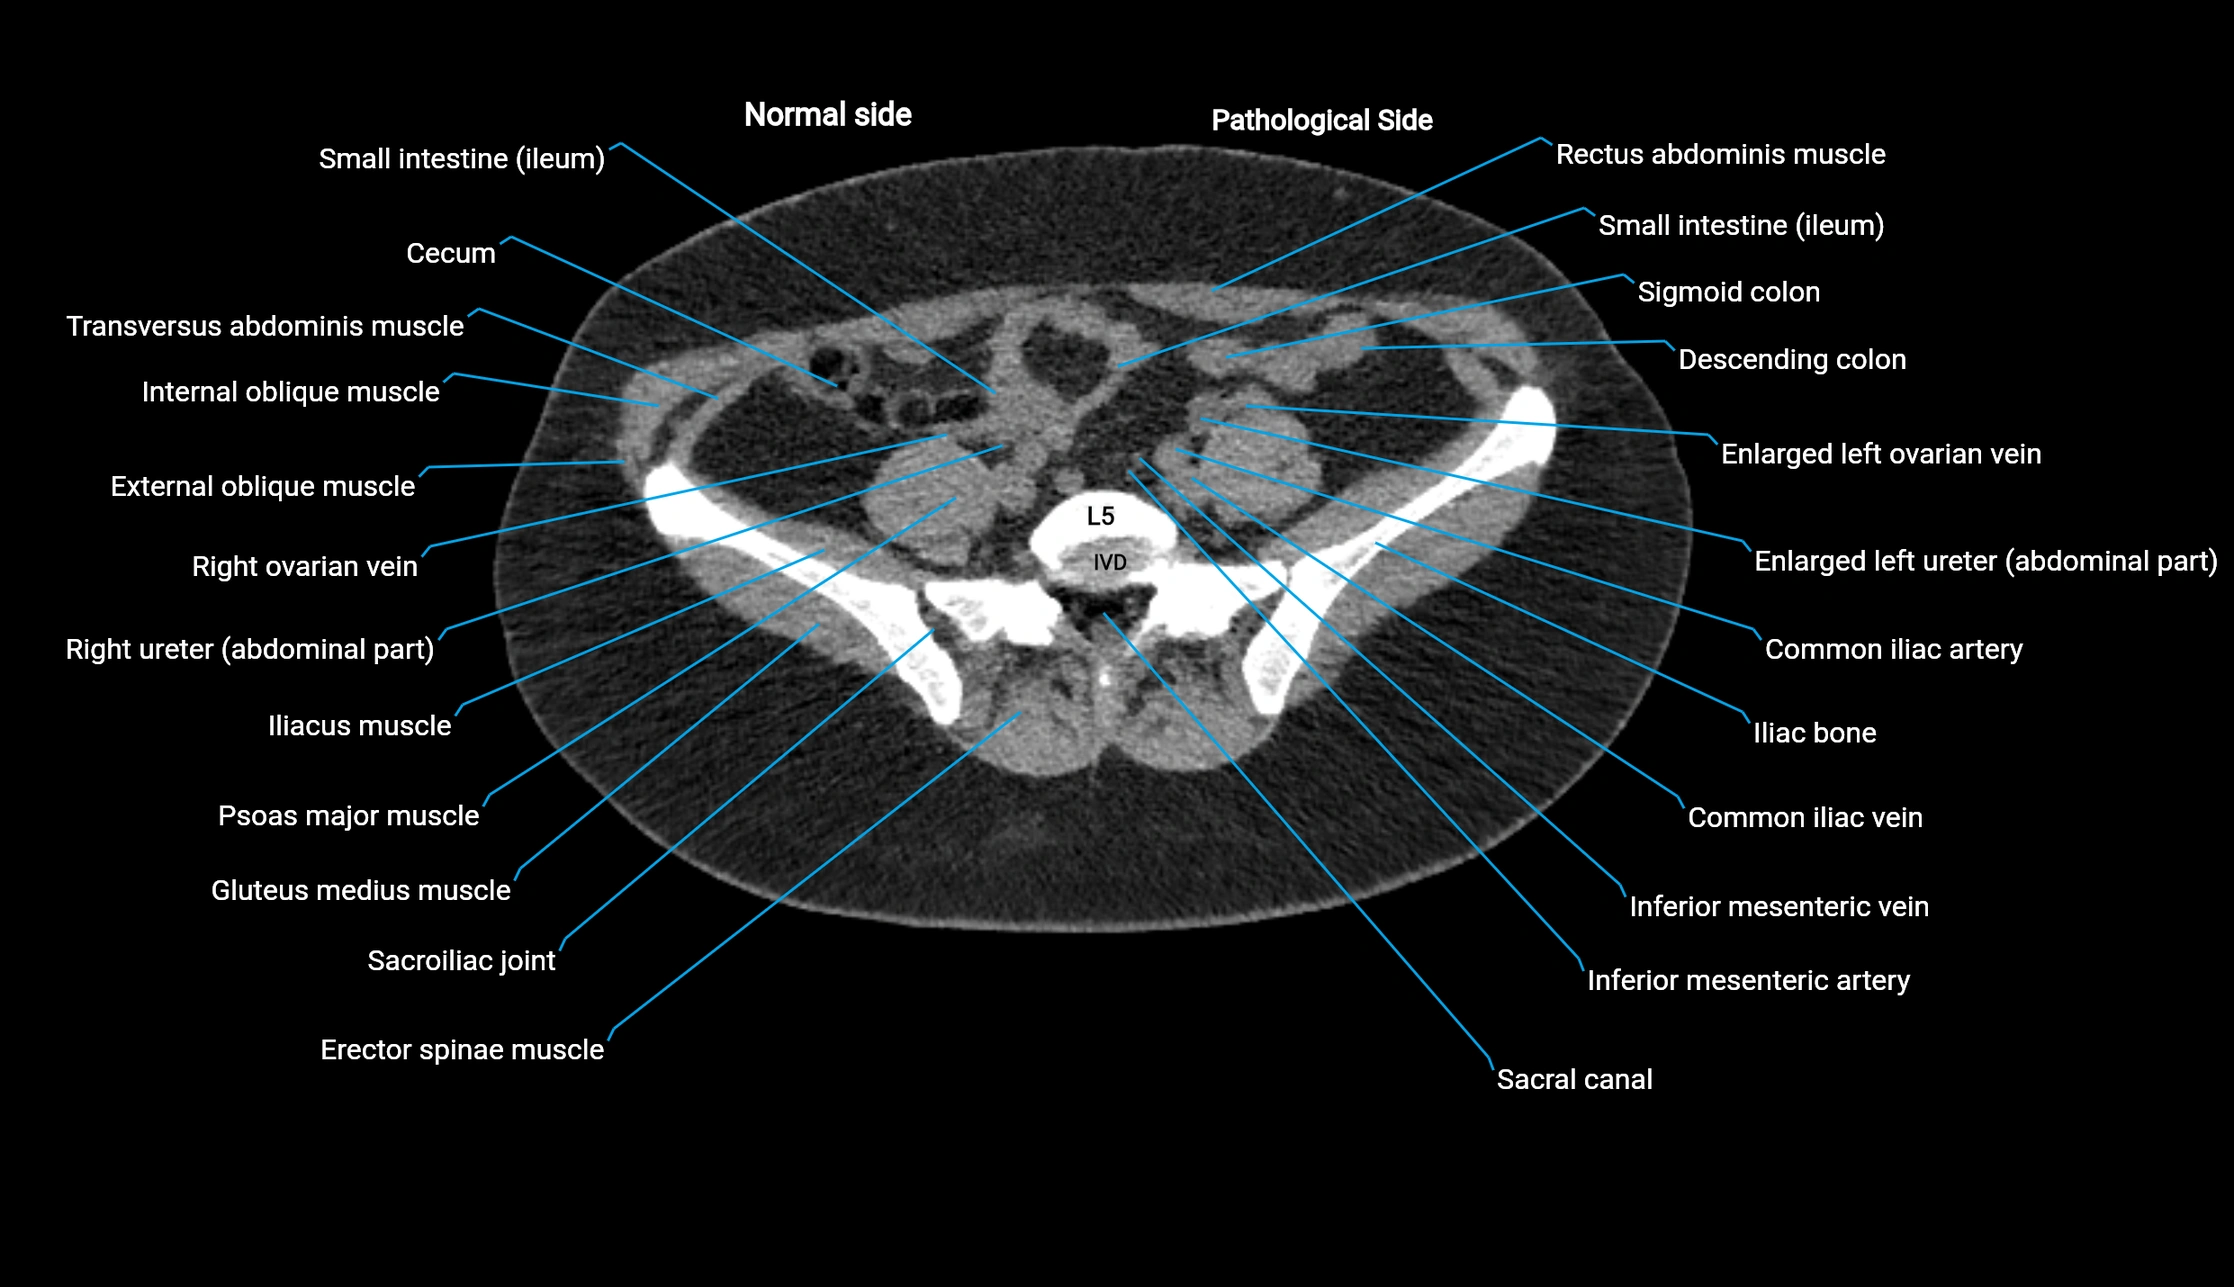

CT image

image